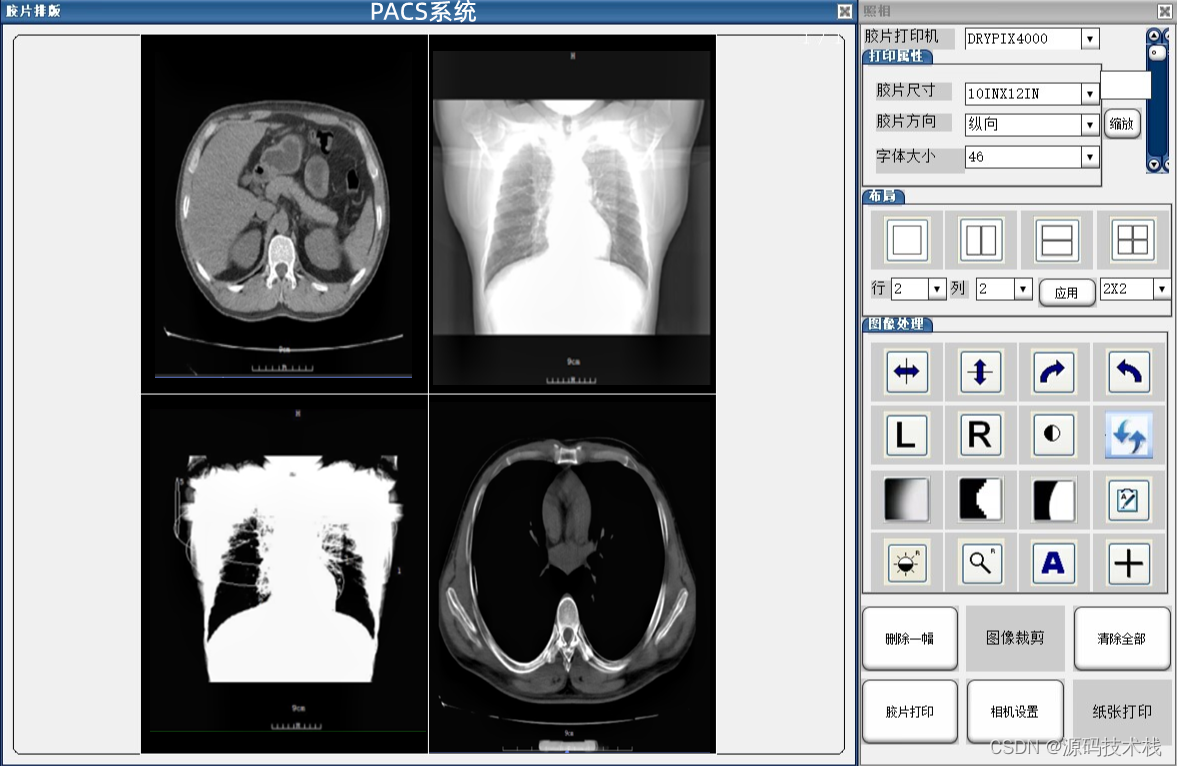

下面就是我们平时大家所做的CT平扫图像:

下面就是三维重建的图像: